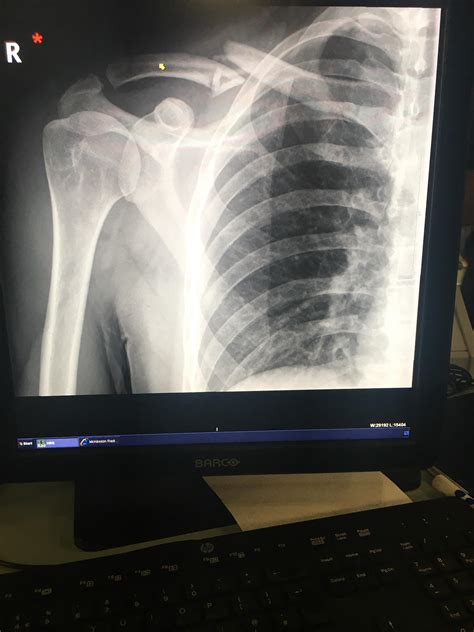

Relieve Collarbone Pain: Causes & Treatment for Active Women